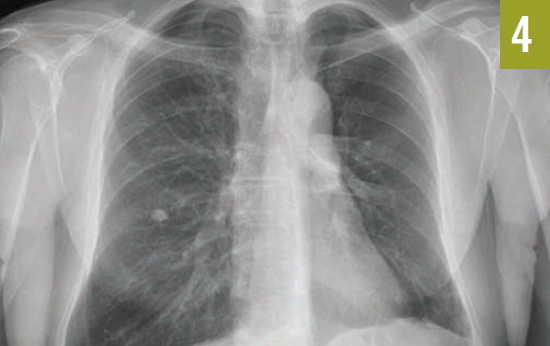

Chest radiographs and computed tomography scans taken at admission showed extensive bilateral pleural calcifications with scattered calcified pulmonary nodules throughout both lung fields (Figures 1 and 2).

Figure 1. A chest radiograph showed extensive bilateral pleural calcifications with scattered calcified pulmonary nodules.

Figure 2. Chest CT scans showed extensive pleural calcifications (solid arrows) with calcified pulmonary nodules (dashed arrow).

The differential diagnosis of pleural calcification includes asbestos pleural disease with calcified pleural plaques, calcifications of prior hemothorax, empyema, exudative pleural effusions, and nonpharmacologic management of pulmonary TB. Pleural calcifications related to asbestos exposure typically arise from the parietal pleura.1 Plaques are visualized on the lateral chest wall along the sixth to ninth ribs and adjacent to the diaphragmatic surfaces of the lungs. There is relative sparing of apices and the costophrenic angles.1,2 Pleural calcifications from hemothorax, empyema, and exudative pleural effusions are localized to the areas of prior involvement.

Our patient presented with bilateral pleural calcifications mostly involving the upper lung fields. These findings were inconsistent with the pleural calcifications seen with asbestos exposure. The pattern of calcification in our patient was highly suggestive of prior pneumothorax treatment for pulmonary TB.